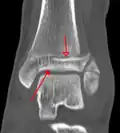

A triplane fracture of the ankle as seen on plain X-ray -

A triplane fracture of the ankle as seen on CT -

A triplane fracture of the ankle as seen on CT